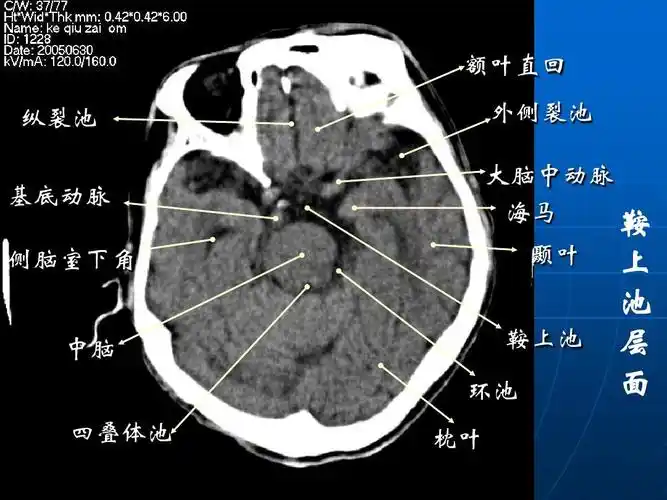

脑池的断面解剖图ppt

纵裂池 基底动脉 侧脑室下角 中脑 四叠体池 枕叶 外侧裂池 大脑中